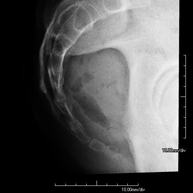

- X-ray arthrography

This X-ray based procedure involves injecting a contrast agent into the joint to detect lesions in certain structures (cartilage, bone, tendons, etc.) by observing the distribution of the contrast agent.

- Pelvis X-ray

This procedure uses X-ray imaging to examine the pelvis, especially the pelvic bones.